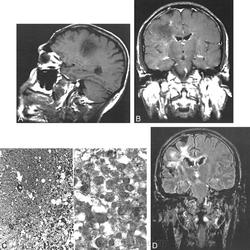

Патоморфологически КСБ отличается образованием преимущественно в белом веществе лобных долей обширных очагов демиелинизации, отдельные из которых окружены характерными кольцами, состоящими из зон полного или частичного разрушения миелина. При их микроскопии отмечаются выраженная дегенерация олигодендроцитов, сопровождающаяся их апоптозом, и мелкоклеточные васкулиты.

С внедрением в клиническую практику методов нейровизуализации головного мозга (в частности, магнитнорезонансной томографии) появилась возможность прижизненной диагностики КСБ. При проведении МРТ в Т2Wрежиме у больных с КСБ в сером и белом веществе головного мозга выявляются гиперинтенсивные очаги различного диаметра, часть из которых окружена гипоинтенсивными концентрическими кольцами. Взаимосвязь между РС и КСБ подтверждают данные C. Wang и соавт., которые при проведении МРТ в динамике у 7 больных с КСБ наблюдали появление новых очагов демиелинизации, характерных для обоих заболеваний.